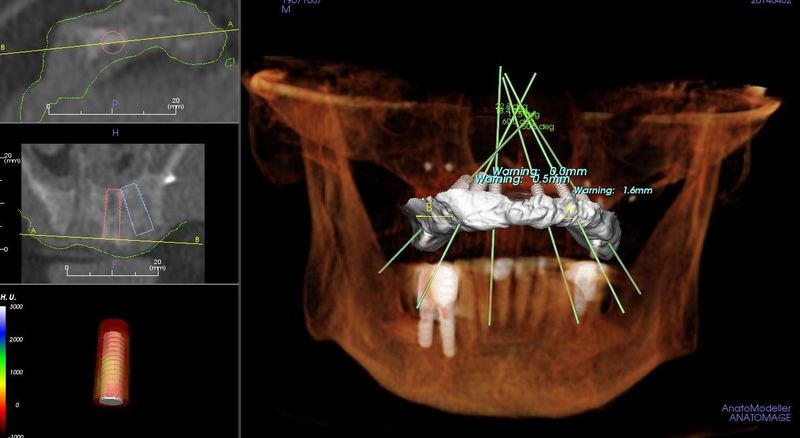

CT Scanner for Optimal Treatment Planning

New iCAT CT scanner offers precise imaging with radiation comparable to traditional x-ray units.  Using this 3D imaging technology the doctor can accurately plan surgery, avoid complications, and create custom implant treament plans.

The CT scanner's imaging allows us to create custom made surgical guides specific to each patient.  These surgical guides allow the precise placement of dental implants for optimal functional and esthetic results.

CT Guided Custom Implant Placment